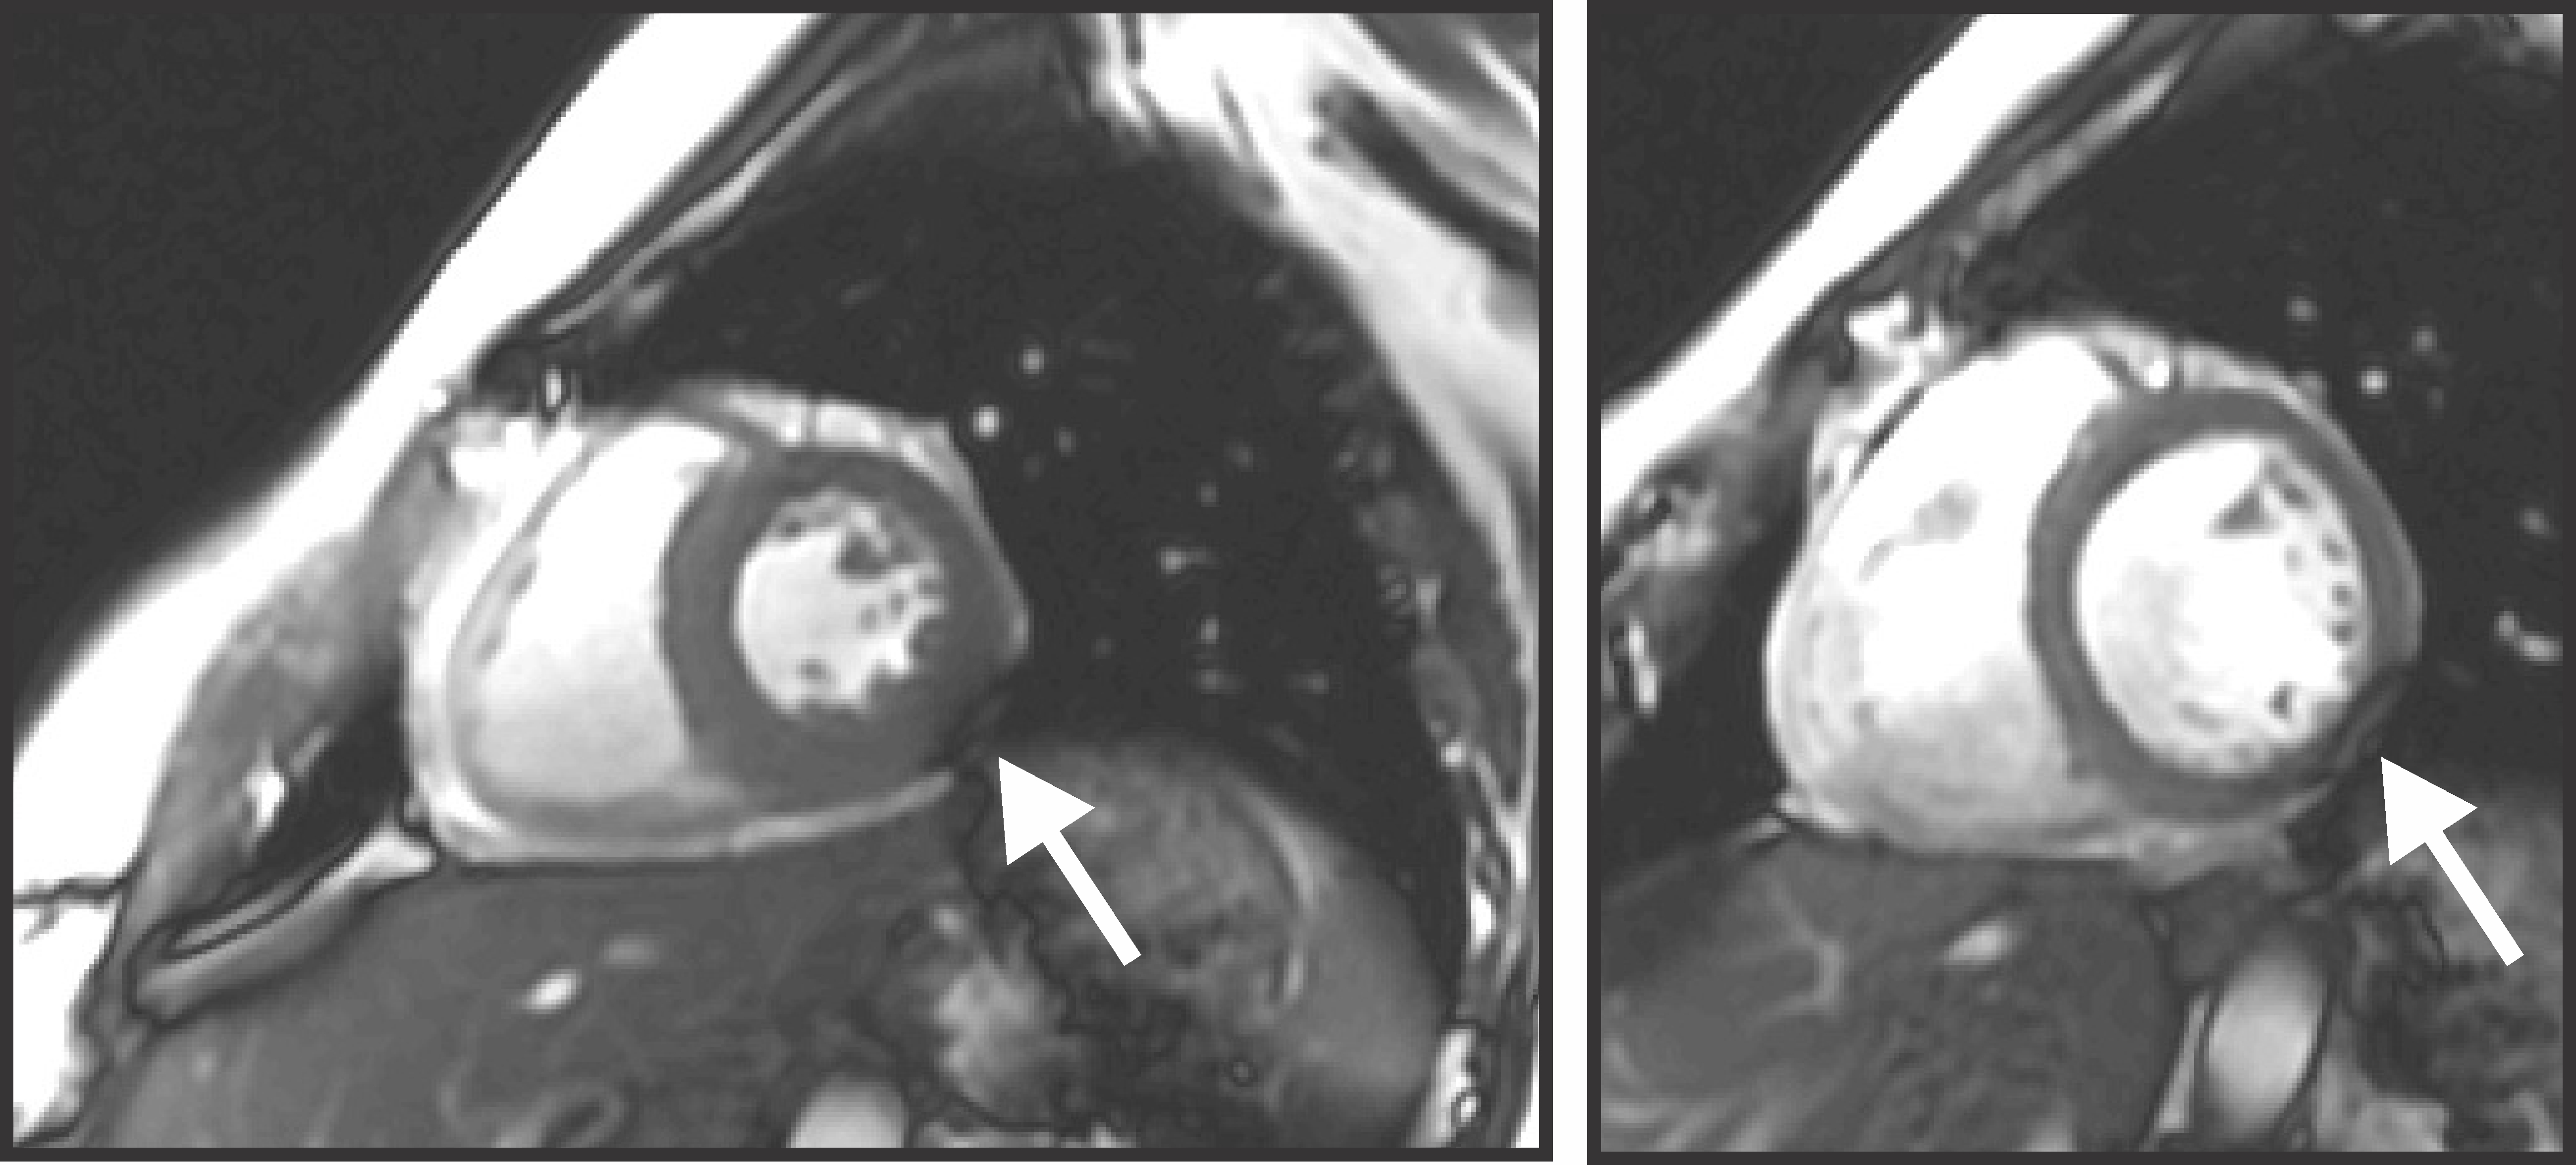

Cardiac functional scans adopting bSSFP sequences at 3 T suffer from dark band artifacts due to B0 inhomogeneity inside the human heart1, 2 (Figure 1). The most effective remedy to mitigate this issue is to homogenize the B0 distribution in the heart via B0 shimming3, typically achieved in MR scanners via spherical harmonic (SH) shim coils up to second- or third-order4. Mattar et al.5 theoretically accessed the potential of global SH shimming in the whole heart and dynamic shimming within local axial slices upon five in vivo B0 maps. Recent work at 7 T from Hock et al.6 compared experimental shim results of these types in the same orientation. Although both studies suggest better results for dynamic shimming, as expected, the associated shim performance on cardiac imaging planes, e.g., short-axis views, remains unknown. Furthermore, in vivo acquired B0 maps in these and other studies2, 4 are constrained by limited sample size, spatial resolution, and the number of slices due to short acquisition time under breath-hold conditions. The consequential limited knowledge of B0 conditions in cardiac imaging planes impedes the development of an optimal shim strategy. We recently presented a customized method for computing high-resolution cardiac B0 maps based on routine CT images7. Here we propose an oblique slicing method to obtain B0 distributions of short-axis views based on simulated B0 maps from a large and diverse population of human subjects. We analyze the B0 conditions in the heart with SH-based B0 shimming in clinically relevant slice orientations to set the stage for developing optimal B0 shim strategies tailored to cardiac MRI.

Fig. 1. Susceptibility-induced artifacts in the myocardium caused by B0 variations in the heart. In vivo cardiac cine images were acquired using a bSSFP sequence with a TR of 3.56 ms after a linear shim provided by the scanner at 3 T. Dark band artifacts (white arrow) are presented in the inferolateral wall of the myocardium in the systolic (left) and diastolic (right) cardiac phases. These artifacts were induced by off-resonance frequencies in the heart.